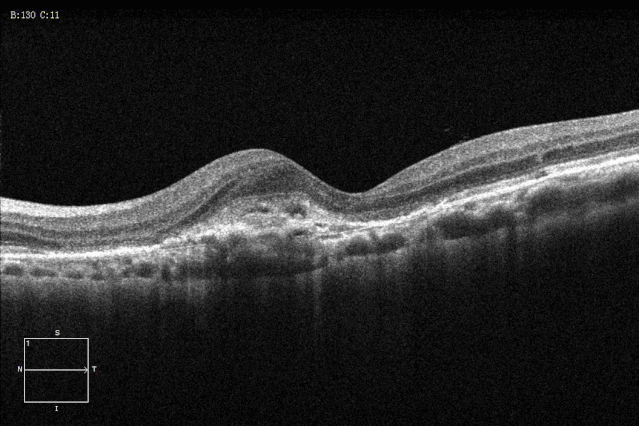

脉络膜新生血管oct

特发性脉络膜新生血管. [病例帖]